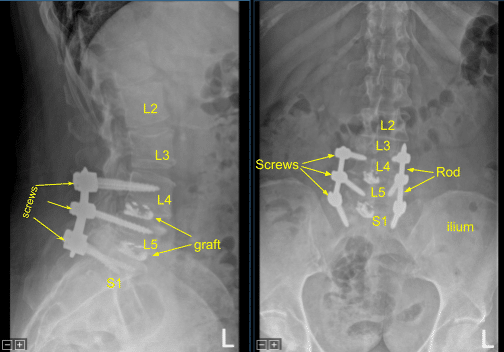

Again, a precut-precontoured titanium rod was placed across the pedicle screw tulips from L4 to S1 and secured with the locking caps which were tightened with a torque and anti torque device. Morselized bony allograft was placed across L5-S1 on the right side for the arthrodesis.

The small dehiscence on the left-sided incision was debrided and the skin was reclosed. All the incisions were cleaned and dried sterilely, and dressings were applied in a sterile manner. A Hemovac canister was applied with suction. C-arm unit was draped sterilely and used for AP and lateral fluoroscopic confirmation of correct hardware and instrumentation positioning, specifically the rod placement.